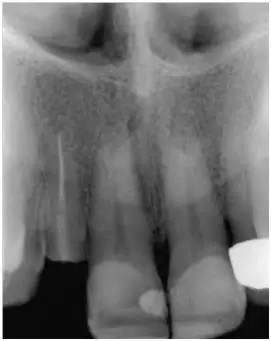

12至22牙的影像學(xué)檢查(圖5);

影像學(xué)檢查:根尖和根中三分一段內(nèi)的根管充填尚可(牙膠和根充糊劑),圓柱形根樁(鈦)位于根上三分之一段,在根中三分之一可見X線阻射性材料(粘結(jié)劑)。

根尖周無病理性變化

根長度約15mm

圖5:外傷9天后的影像學(xué)檢查:12牙牙冠在釉牙骨質(zhì)界水平處折斷并且可以看到根管充填和一個折斷的鈦根樁。所有牙齒均顯示輕度的水平向骨吸收,根尖周未發(fā)現(xiàn)異常。11至22牙牙冠被修復(fù)過。